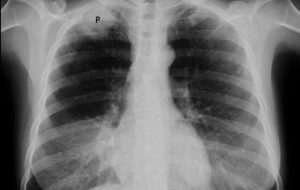

Воспалительные процессы в паренхиме легких, распространяющиеся из бронхов и бронхиол, называются бронхопневмонией. Другое ее название — лобулярная пневмония. Согласно международному классификатору, при постановке диагноза используется код МКБ-10 J18.0. Разница между бронхиолитом и другими типами заключается в том, что он имеет бронхиальное происхождение, при этом стенка бронхов является основным источником воспаления. Этиология и факторы риска Причина …